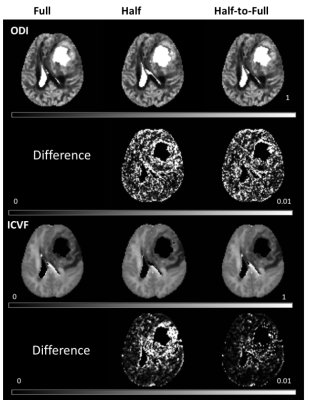

The half q-space under-sampling scheme did not significant sacrifice the accuracy of quantitative maps of advanced diffusion model but could accelerate the acquisition by 2 fold. In addition, a symmetrically data copy step is needed to improve the estimation accuracy.

Figure 1. ODI and ICVF maps (NODDI model) of three different schemes (Full, Half and Half-to-Full) and their corresponding percent of square coefficient of variation (CV) for a patient.